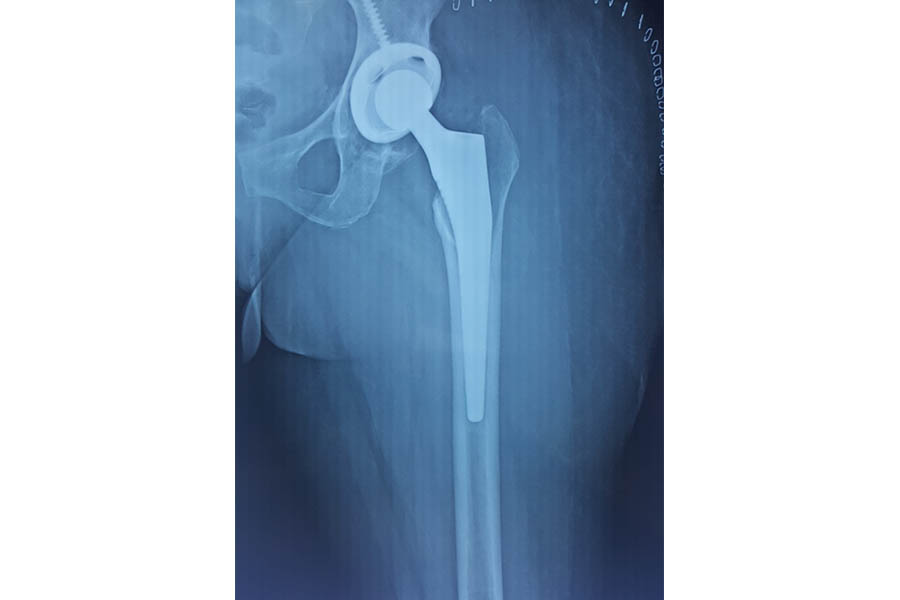

Total Hip Replacement

Case 1